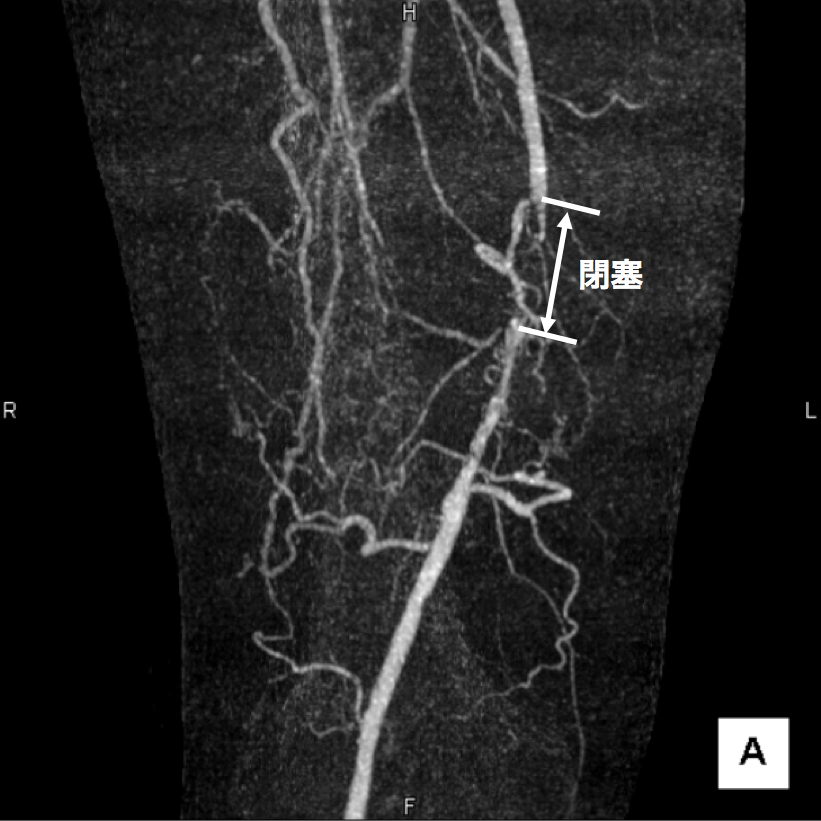

3、造影CT検査 造影剤を点滴しながらCTを撮像することで、血液の流れ、血管の状態などを把握します。情報量が多く治療方針を決定する場合に役立つので当院では特に力を入れている検査です。(図2、3、4)

【図3】下肢造影CT検査 この画像は血管の立体的な走行の把握に有用です。 右足大腿部の血管に強い石灰化(動脈硬化の変化)があります。

【図4】下肢造影CT検査 サブトラクションという画像の処理を行うと、血流が途絶えており、血管が完全に閉塞していることがわかります。